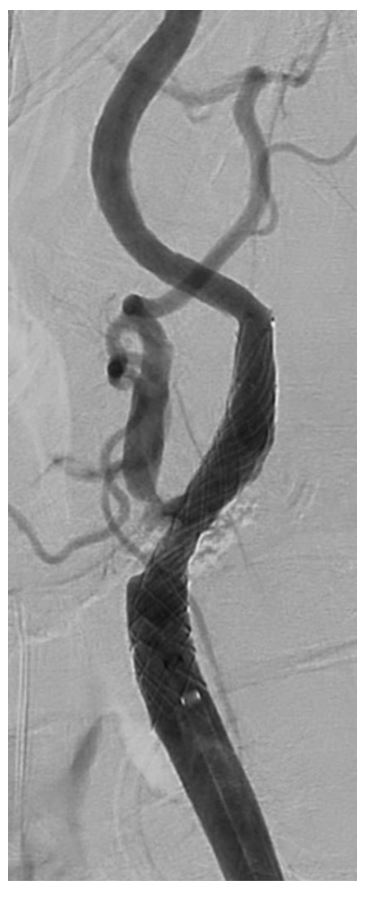

Figure 4: Digital Subtraction Angiography of Left ICA post-stenting.